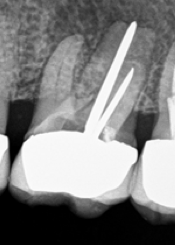

Sign of separated instrument?

Sometimes a dentist can break off a piece of the small drill bit or file in your tooth. These tools are very delicate and must be used with great care. Ideally the dentist will get the broken piece out. If it’s not possible to get it out, did the dentist at least tell you about this?